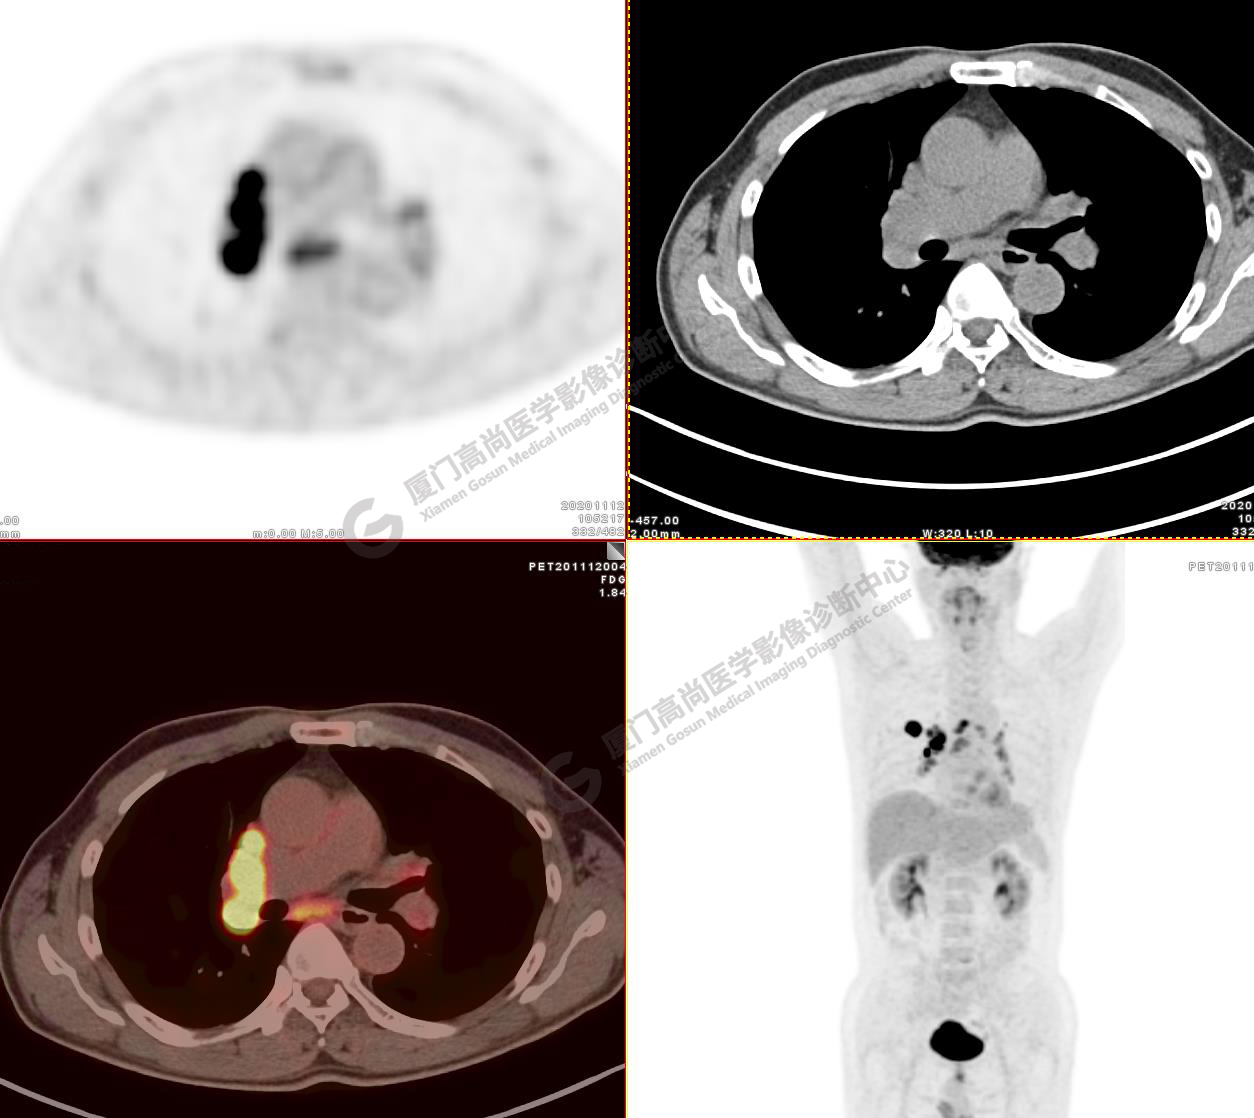

病例2:某男士,53歲,2020年4月單位體檢,CT,發(fā)現(xiàn)右肺上葉結(jié)節(jié),性質(zhì)待定

右肺上葉前段見一類圓形實(shí)性結(jié)節(jié),大小約2.8x2.6cm,邊緣見分葉、毛刺,前段支氣管阻塞。FDG攝取增高,SUVmax16.5,右肺門及縱隔見多發(fā)腫大淋巴結(jié), FDG攝取增高,SUVmax13.1,遠(yuǎn)處未見FDG高攝取病灶 。

影像診斷:右肺上葉周圍型肺癌并右肺門及縱隔淋巴結(jié)轉(zhuǎn)移。

( TNM分期,T1cN2M0 ⅢA期)

病理診斷 :低分化腺癌